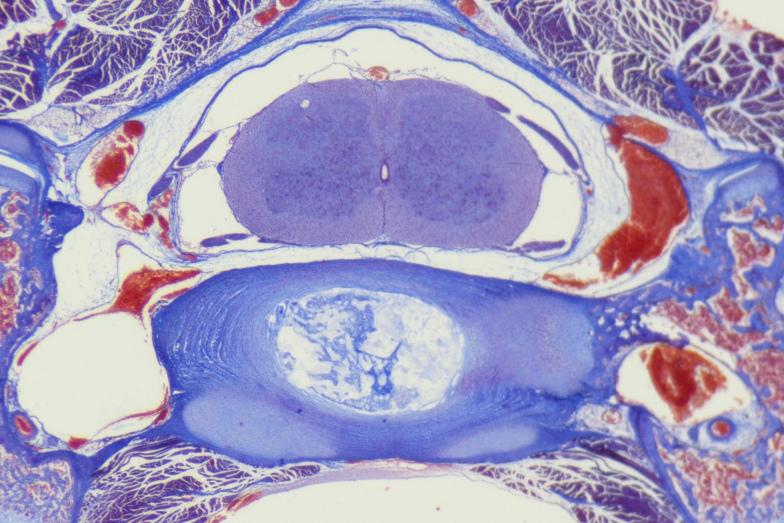

應用範例